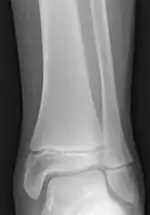

صفحه رشد استخوان(به انگلیسی: Growth plate) یا Physis صفحه ای غضروفی از جنس غضروف شفاف (هیالن)* است که مابین دو قسمت اپیفیز و دیافیز استخوانهای بدن قرار دارد و رشد طولی آنها را میسر میسازد.[1]

صدمه صفحه رشد

شکستگیها یا صدماتی که در دوران کودکی و قبل از بسته شدن صفحه رشد اتفاق می افتد میتواند فعالیت آن را متوقف یا کند یا تغییر دهد. این صدمات میتواند عوارضی مانند توقف رشد، کوتاهی اندام، انحراف محور طولی استخوان و نیز تغییر شکلهای مفصلی مانند پای پرانتزی، پای ضربدری ویا بیرونخمیدگی ساعد بوجود آورد.